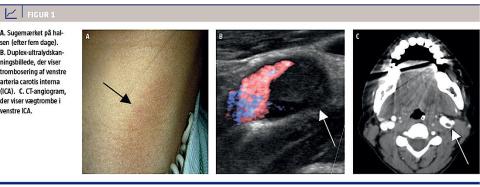

En 35-årig kvinde, som ikke havde nogen vaskulære risikofaktorer ud over rygning, blev indlagt på Medicinsk Afdeling, Dronning Ingrids Hospital, Nuuk, Grønland. Patienten havde akut udviklet nedsat kraft og sensibilitet i de højresidige ekstremiteter, National Institute of Health Stroke Scale (NIHSS) 6. På hendes hals fandt man et sugemærke, hvis udbredelse svarende til den øvre del af venstre musculus sternocleidomastoideus, som hun havde fået i forbindelse med et kys på halsen 12 timer forinden (Figur 1A).

I det følgende døgn progredierede symptomerne til hemiparalyse og afasi (NIHSS 27). En ny CTC viste et stort venstresidigt arteria cerebri media-infarkt. Ved en Duplex-UL-undersøgelse afsløredes en nærokklusion af venstre ICA i niveau med sugemærket på halsen (Figur 1B). En CT-angiografi viste en ustabil vægtrombe i venstre ICA (Figur 1C). Evakuering til Rigshospitalet med henblik på endovaskulær eller karkirurgisk behandling kom ikke i betragtning på grund af trombens ustabilitet. Antikoagulationsbe-